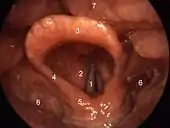

![]() عرض باستخدام "منظار الحنجرة" للجزء الداخلي من الحنجرة (الطية الطرجهالية اللسان مزمارية موسومة في وسط اليمين). عرض باستخدام "منظار الحنجرة" للجزء الداخلي من الحنجرة (الطية الطرجهالية اللسان مزمارية موسومة في وسط اليمين). | |